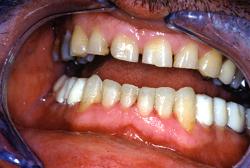

Couronnes tout céramique. Présentation d’un cas clinique : Patient d'une quarantaine d'année bruxomane, présentant des douleurs cervicales et des céphalées matinales. Il existe aussi une perte de la dimension verticale d'occlusion.

Patient d'une quarantaine d'année bruxomane, présentant des douleurs cervicales et des céphalées matinales.

Il existe aussi une perte de la dimension verticale d'occlusion.

Absence de visibilité des dents supérieures lors du sourire forcé

Vue intra-buccale en occlusion

L'espace de repos est très important. La lèvre supérieure est tombante